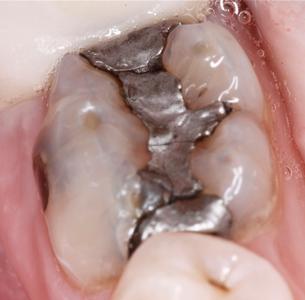

We removed this patient's amalgam fillings and replaced them with natural looking composite fillings.

Before